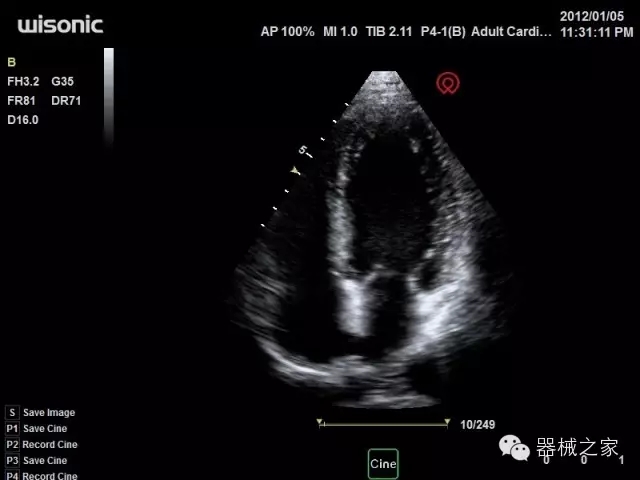

臨床圖片賞析

產(chǎn)品特點(diǎn)

·全球目前唯一一款配備主機(jī)雙探頭接口,整機(jī)重量(含電池)在5公斤以內(nèi)的便攜式彩超;

·獨(dú)有的HoloTM PW 實(shí)時(shí)3取樣門PW成像技術(shù),精確進(jìn)行血管診斷;

·一鍵優(yōu)化B、Color、PW,Auto Doppler自動(dòng)識別血管位置、偏轉(zhuǎn)角度等,提高工作效率;

·30°超廣角精細(xì)偏轉(zhuǎn)成像技術(shù),更優(yōu)異的頻譜圖像;